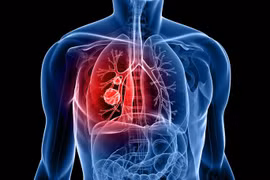

(GLO)- Theo cảnh báo từ các nhà khoa học Anh, trên thế giới có 250 ngàn người chết mỗi năm do bệnh ung thư phổi dù không hút thuốc, mà vì họ hít khói xe và khói từ nhiên liệu hóa thạch.

Chi phí điều trị 5 nhóm bệnh là ung thư phổi, ung thư đường tiêu hóa-hô hấp trên, bệnh tắc nghẽn mạn tính, nhồi máu cơ tim, đột quỵ tại Việt Nam chiếm khoảng 1% GDP (khoảng 67 nghìn tỷ đồng mỗi năm).